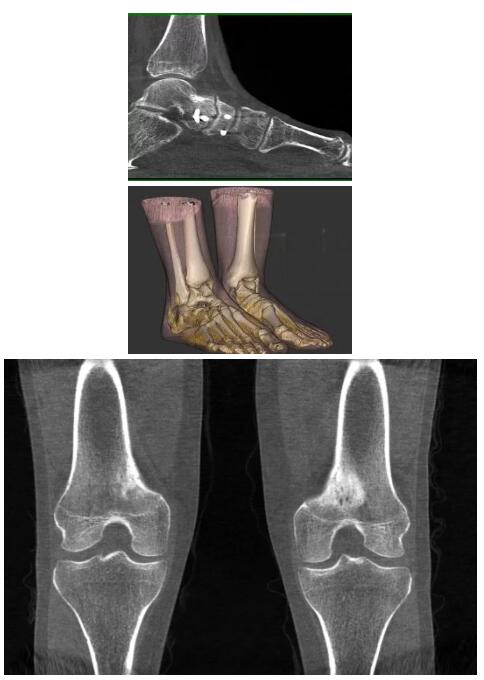

比如上面這款專用于足部和踝部掃查的CT成像系統(tǒng),患者在進(jìn)行CT掃查時只需要站在上面即可,雙腳站或者單腳站都可以,當(dāng)然,如果患者不是那么方便站著做完CT掃查,也可坐在上面。

這款CT掃查系統(tǒng)自帶屏蔽裝置,它的體積非常小,僅需要極小的空間即可,并不像常規(guī)CT那樣需要一間單獨(dú)的檢查室。此外,這種CT掃查的速度非???,僅需30秒左右可以完成檢查,輻射劑量相對常規(guī)的CT要少許多,尤其適合醫(yī)院的骨科使用。

而患者站著做足部或者踝部做CT檢查還有個好處是,可以檢查患者在負(fù)重的情況下,骨關(guān)節(jié)的真實(shí)情況,而躺著做CT掃查時未必能看出來。負(fù)重CT掃查特別是對于受傷的運(yùn)動員或者舞蹈員來說意義更大,能夠更準(zhǔn)確地評估傷情,幫助他們盡早復(fù)原。

以下是這些“特立獨(dú)行”的CT所拍出來的圖像: